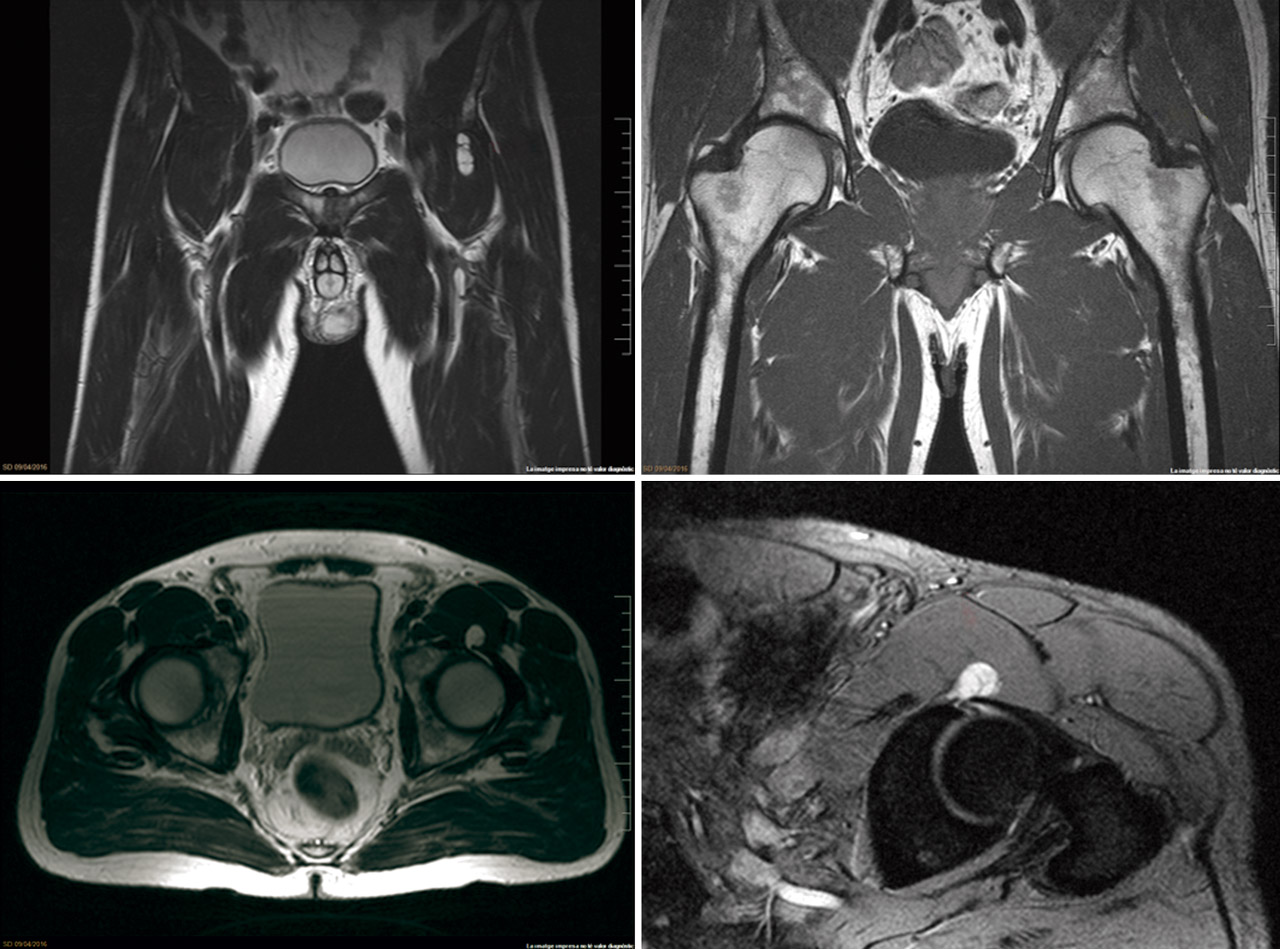

Presentamos el caso de un varón de 48 años, instructor de tenis profesional, sin antecedentes clínicos relevantes. Consulta por coxalgia izquierda incapacitante durante la actividad laboral de unos 18 meses de duración. El examen físico mostró dolor en flexión y rotación interna de la cadera izquierda y una prueba de choque positiva. Se realizaron radiografías para evaluar la presencia de morfologías que pudieran predisponer a un pinzamiento femoroacetabular (Figura 1). No se observó morfología anormal o signos de osteoartritis. El tratamiento inicial incluyó la prescripción de antiinflamatorios no esteroideos (AINE) y la modificación de la actividad física. Se realizó una resonancia magnética (RM) para completar el estudio. Los resultados de la RM no identificaron alteraciones morfológicas o cambios de señal en la cabeza femoral que pudieran sugerir necrosis ósea, focos de osteocondritis, fracturas por estrés, edema óseo u osteoporosis transitoria. Se identificó una lesión del labrum anterior con un quiste paralabral asociado a esta, de 32 × 17 mm (Figura 2). Después de 3 meses de tratamiento conservador sin mejoría clínica, se propuso la escisión quirúrgica y la reparación del labrum. La extirpación quirúrgica se realizó a través de artroscopia mediante técnica fuera-dentro. Todas las estructuras óseas en el compartimento central no mostraron signos patológicos. Se observó una lesión del labrum en su zona anterosuperior (zona 2)(2). En el compartimento periférico, se identificó una gran lesión quística que rodeaba el borde anterosuperior del labrum y el acetábulo (Figura 3). La extirpación completa del quiste se realizó artroscópicamente utilizando material específico para la artroscopia de cadera. No se registraron complicaciones intraoperatorias. La reparación labral se realizó con un sistema de anclaje All-Suture® de tipo Y-Knot® (Conmed). Se inició el protocolo de fisioterapia postoperatoria habitual de nuestro centro, permitiendo la carga parcial con dos muletas al momento del alta con progresión gradual a peso completo en un periodo de 2-3 semanas, seguido de un protocolo de rehabilitación para conseguir el rango completo de movilidad articular y lograr la fuerza completa de la extremidad. En un periodo de 3 meses, el paciente regresó por completo a la actividad física. No se observaron complicaciones.

Figura 2. A: imagen coronal de STIR que muestra la lesión quística (flecha roja) que ocupa el músculo psoas; B: desgarro labral (flecha amarilla); C: imagen axial T2 que compara ambas caderas. La lesión quística (flecha roja) se identifica en el espacio articular anterior de la cadera izquierda; D: T2 imagen sagital del quiste labral (flecha roja) inferior a la espina iliaca anteroinferior.